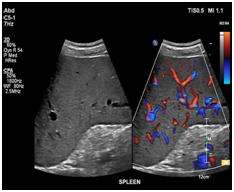

Your doctor has ordered an ultrasound of your abdomen. Ultrasound is a safe and painless procedure that uses sound waves to assess the structure of your internal body organs. The scan can help diagnose such medical conditions as abdominal masses, gallbladder disease and gallstones, as well as problems in the liver, kidneys, pancreas or spleen.